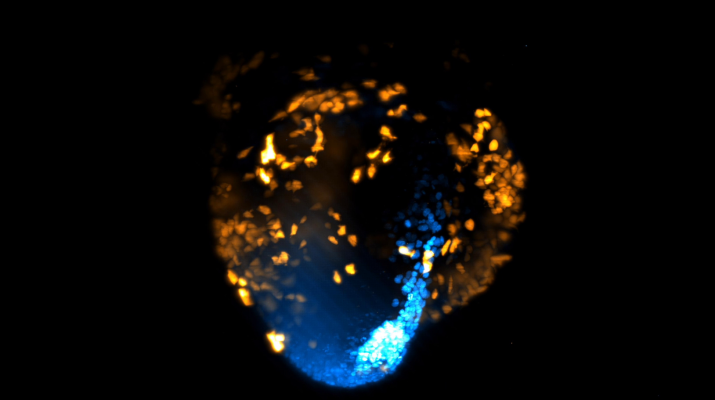

Para isso, foi utilizada a técnica de microscopia avançada de lâmina de luz, em que um fino raio de luz ilumina o tecido vivo e gera imagens 3D nítidas. A equipe usou marcadores fluorescentes nas células do músculo cardíaco, gerando o brilho visto nos vídeos da pesquisa.

O time-lapse mostra 40 horas de desenvolvimento celular, registrado a cada dois minutos. Essas imagens mostraram à comunidade científica onde as primeiras células que compõem apenas o coração apareceram no embrião.